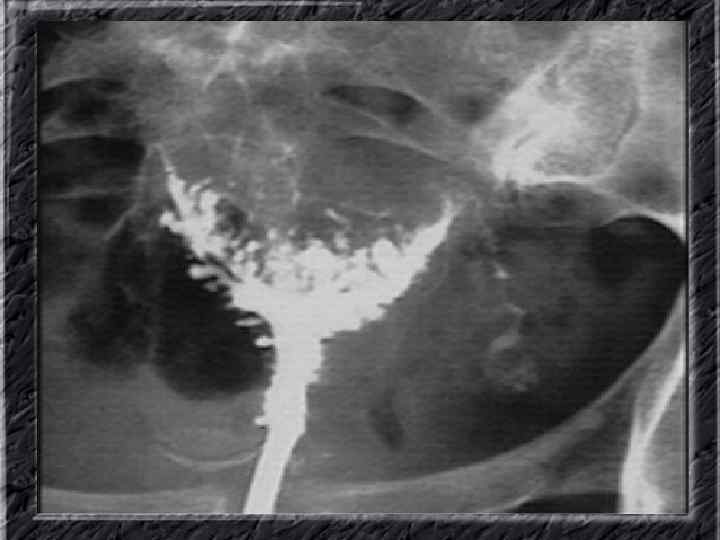

Названия слайдов: • • • Слайд 1. Титульный лист. Слайд 2. Лапароскопия: вид неизмененной матки. Слайд 3. Гистеросальпингография: тень полости неизмененной матки при ее заполнении рентгеноконтрастным веществом Слайд 4. Ультрасонография: вид эндометрия в разные фазы менструального цикла. Слайд 5. Матка: два отдельных тела имеют общую шейку; макропрепатат. Слайд 6. Гистерография: разделение тени полости матки выемкой, расположенной в области дна. Слайд 7. Лапароскопия: удвоение матки. Слайд 8. Ультрасонография: удвоение матки. Слайд 9. Гистерография: четкие неровные контуры дефектов наполнения полости матки при синехиях. Слайд 10. Эндометриальная гиперплазия: полость матки выстлана пышным, подобным пальмовым листьям гиперпластическим эндометрием; макропрепарат.

Названия слайдов: • • • Слайд 11. Гиперплазия эндометрия: железистый полип с очагами геморрагий; макропрепарат. Слайд 12. Ультрасонография: однородный эндометрий средней плотности с четкими ровными контурами при неактивной форме железистой гиперплазии эндометрия. Слайд 13. Ультрасонография: гипоэхогенная зона округлой формы в эхоизображении эндометрия — железистый полип. Слайд 14. Ультрасонография: железистый полип эндометрия в виде эхонегативного образования. Слайд 15. Гистерография: характерные изменения контуров полости матки при железистой гиперплазии эндометрия. Слайд 16. Гистерография: изменение формы и зубчатость контуров полости матки при эндометриозе. Слайд 17. Гистерография: изменение формы и зубчатость контуров полости матки при эндометриозе. Слайд 18. Гистерография: направленные перпендикулярно к контурам полости матки контрастированные канальцы. Слайд 19. Гистерография: затек рентгеноконтрастного вещества в правом углу матки при эндометриозе.

Названия слайдов: • • • Слайд 51. Ультрасонография: интерстициальный и истмический отделы маточной трубы. Слайд 52. Лапароскопия: неизмененная правая маточная труба. Слайд 53. Ультрасонография: многокамерная форма сальпингита. Слайд 54. Лапароскопия: относительно равномерное утолщение маточной трубы при гидросальпинксе. Слайд 55. Лапароскопия: вид маточной трубы при гидросальпинксе. Слайд 56. Гистеросальпингография: неравномерное расширение и деформация маточных труб. Слайд 57. Прервавшаяся трубная беременность: плод; макропрепарат. Слайд 58. Гематосальпингс, развившийся вследствие внутреннего разрыва плодо-вместилища при трубной беременности; макропрепарат. Слайд 59. Лапароскопия: значительное увеличение участка маточной трубы при трубной беременности. Слайд 60. Лапароскопия: скопление крови в полости малого таза в результате трубного аборта.